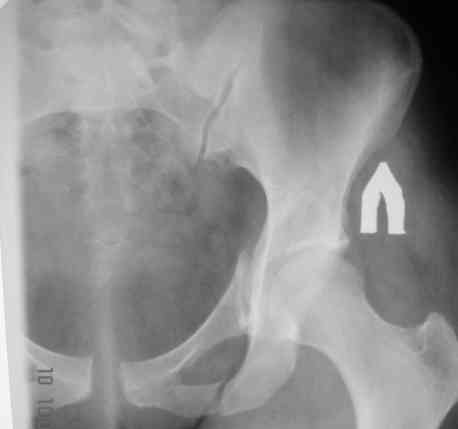

В больнице вправили вывих бедра, три недели на вытяжении. Беспокоят боли в левом тазобедренном суставе и левом крестцово-подвздошном сочленении. Ходит с тростью. Снимок - в приложении. Направил на КТ, заключение: разрыв симфиза и левого крестцово-подвздошного сочленения, переломы крыши и заднего края вертлужной впадины, горизонтальной ветви лонной кости слева.

Уважаемый д-р Булахтин, на мой взгляд единственное повреждение требующее синтеза - застарелый разрыв лона. Низкий перелом передней колонны безопасен, повреждения свода не вижу, неясно что было сзади (скорее боковая масса)лучше сделать обзорный снимок прямой и Inlet.

Т.о. пластинка на лоно сейчас, про впадину забыть (важен только факт вывиха, а был ли он?)

Если был задний вывих, то повреждение должно локализоваться сзади. В данном случае перелом спереди, как результат сдавления лонного сочленения.

Синтез лонного сочленения восстановит стабильность тазового кольца.